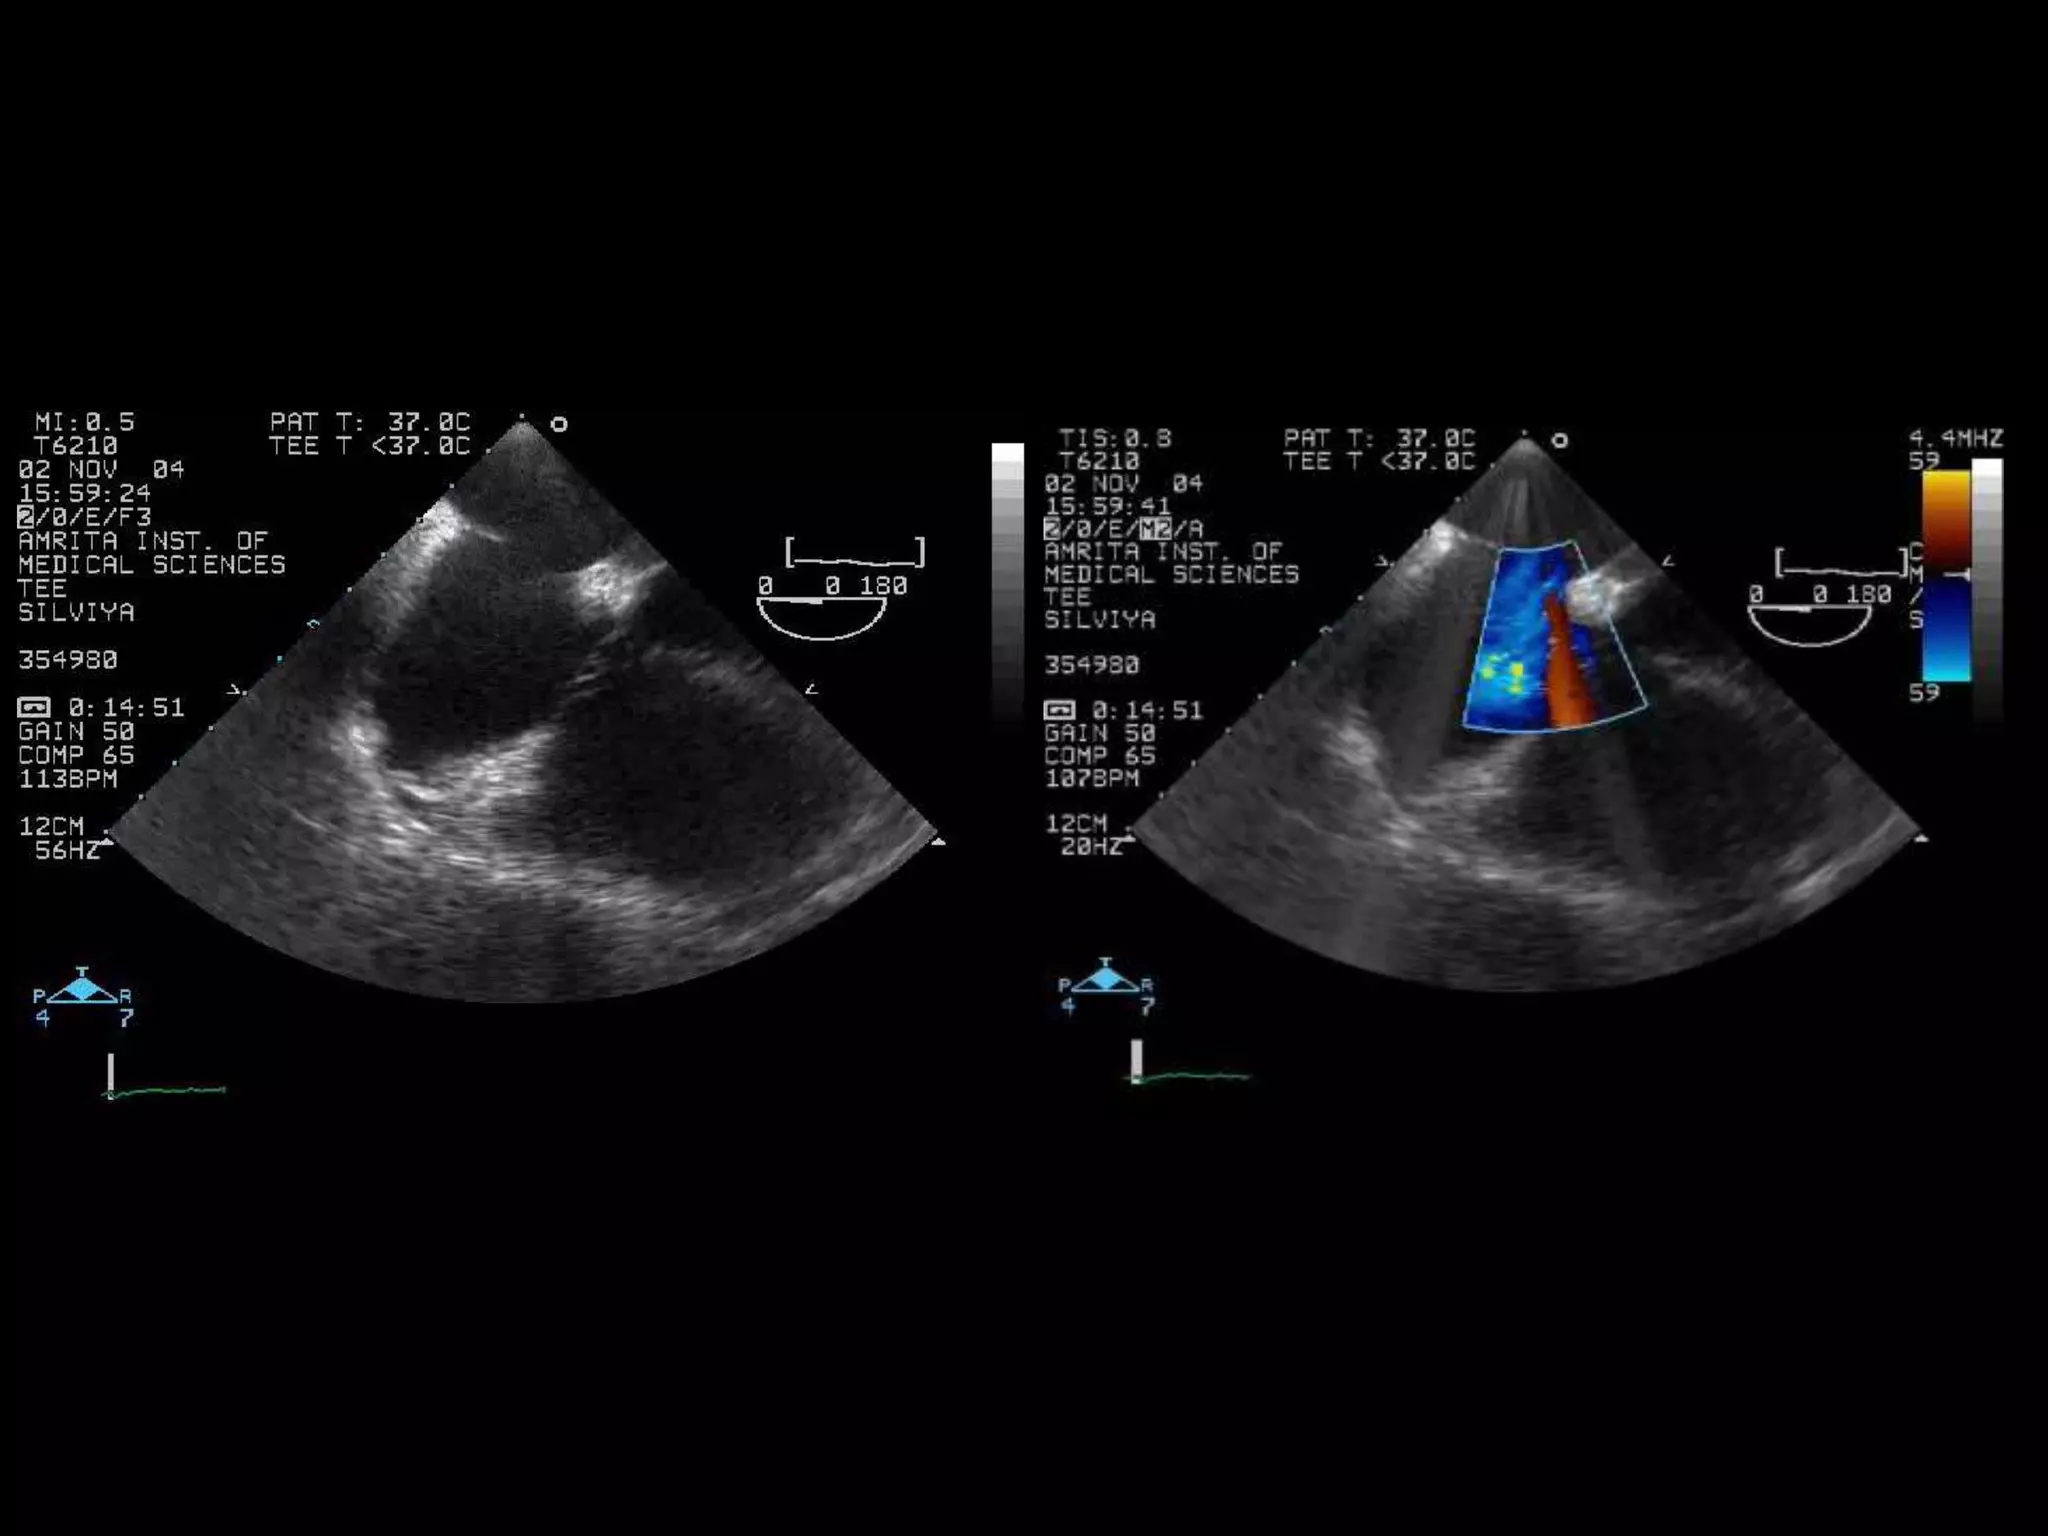

Special tee views for Inferoposterior

rims

No Infero posterior rim with probe in normal position

Catheter Closure of Atrial Septal Defects With Deficient IVC Rim Under

TEE Guidance

K.S. Remadevi, MD, FNB, Edwin Francis, DM, and Raman Krishna Kumar, DM, FACC .

Catheterization and Cardiovascular Interventions (2008)

Retroflexed probe in the stomach and bought towards the esophagus and viewed

In the 70-90o view